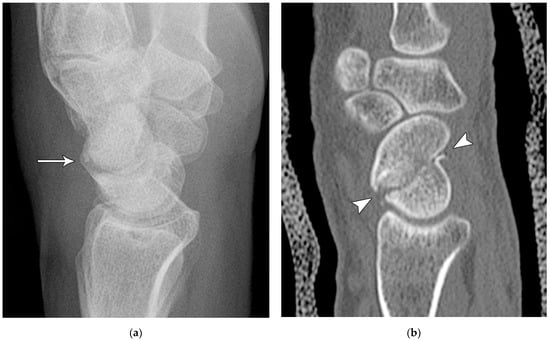

Figure 4. (a) Lateral radiograph of the wrist showing Humpback deformity (arrow) after a scaphoid fracture. (b) Sagittal CT reformation of the wrist showing the full extent of a humpback deformity with dorsal prominence at the site of the scaphoid fracture (arrowheads); image courtesy of Frank Gaillard, Radiopaedia.org, rID: 18269.

The majority of scaphoid fractures (70%) occur through the waist of the scaphoid, with 10% of scaphoid fractures involving the distal third, and 20% involving the proximal third (Figure 2 and Figure 3) [2,14]. With a scaphoid waist fracture, dorsal prominence at the fracture site due to dorsal angulation is known as humpback deformity (Figure 4). This deformity is important to recognize, as it needs to be more aggressively managed due to high risk of nonunion [15]. Additionally, if the two fragments unite with a humpback deformity, it may further destabilize the wrist. This humpback deformity may also be associated with dorsal intercalated segment instability (DISI), which will be covered in more detail later.